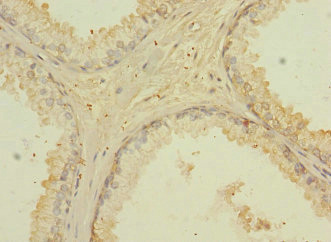

Immunohistochemistry of paraffin-embedded human prostate cancer using CSB-PA745871ESR1HU at dilution of 1:100